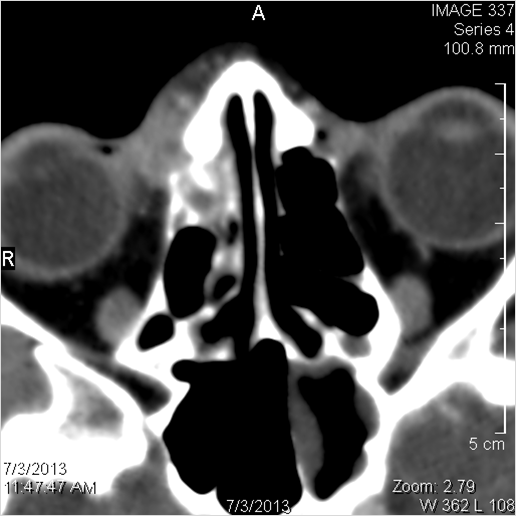

Sinuses

There is mucoperiosteal thickening in the sinuses. [Yes/No]

There is bone erosion along the walls of any affected sinuses. [Yes/No]

Findings are consistent with the clinical diagnosis of invasive fungal sinus disease.